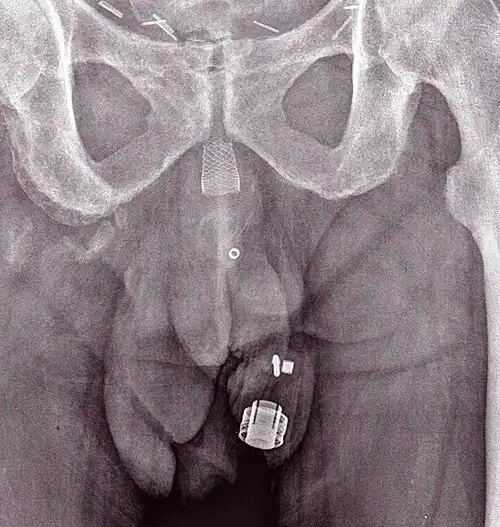

Ein Röntgenbild des implantierten ZSI 375. Das Gerät ist deaktiviert – die Feder wird unter der Oberseite des Zylinders zusammengedrückt. Der Patient ist inkontinent. -

Ein Röntgenbild des implantierten ZSI 375. Das Gerät wird aktiviert – die Feder wird oben am Zylinder dekomprimiert. Der Patient ist kontinent. -